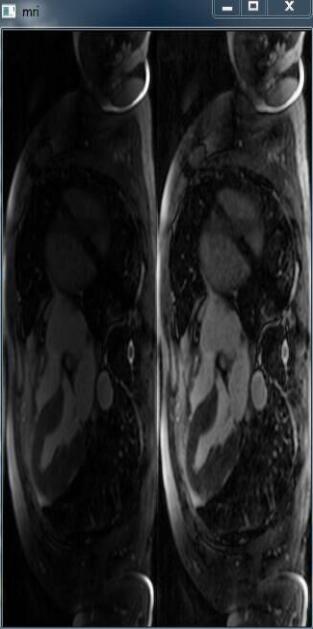

import numpy as npimport cv2 mri_img = np.load('mri_img.npy') # normalizationmri_max = np.amax(mri_img)mri_min = np.amin(mri_img)mri_img = ((mri_img-mri_min)/(mri_max-mri_min))*255mri_img = mri_img.astype('uint8') r, c, h = mri_img.shapefor k in range(h): temp = mri_img[:,:,k] clahe = cv2.createCLAHE(clipLimit=2.0, tileGridSize=(8,8)) img = clahe.apply(temp) cv2.imshow('mri', np.concatenate([temp,img], 1)) cv2.waitKey(0)

均衡化前、后對比效果